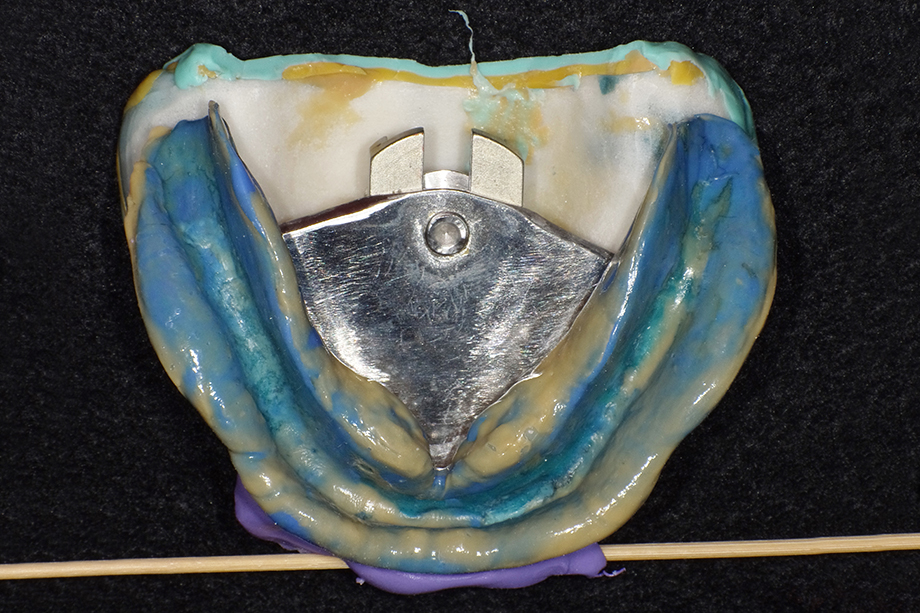

Klinischer Fall einer Totalprothese von Dr. Fumiaki Yamazaki mit der zahntechnischen Umsetzung von Toru Odagaki

Aufstellung der Zähne unter Berücksichtigung der hydrostatischen Stabilität bei größtmöglicher Ästhetik im Frontzahnbereich und Stabilität im Seitenzahnbereich. Speziell bei der Unterkieferprothese.

Das Easy Set Up Konzept ermöglicht ein einfaches Aufstellen.

Um die Saugeffizienz der Unterkieferprothesen zu optimieren, ist es essentiell, dass die Prothesenränder so gut wie möglich abschließen. Dies gewährleistet eine okklusale Stabilität der Prothese. Hierzu ist eine funktionale Form der konfektionierten Prothesenzähne wichtig.